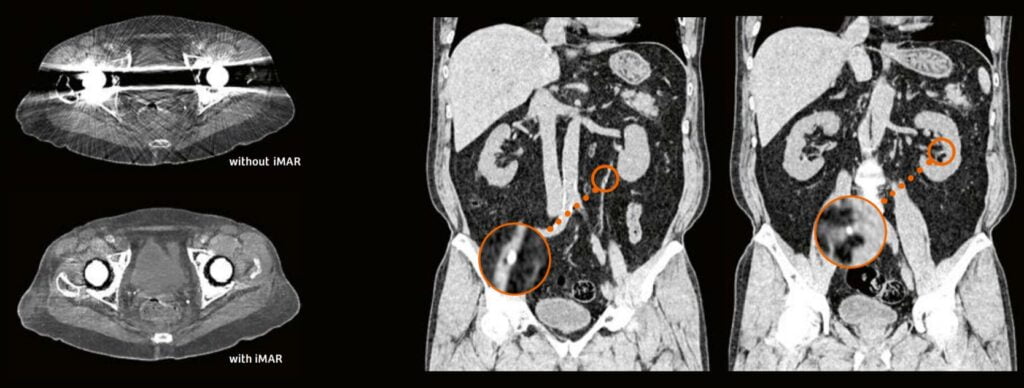

Tomografia computerizată (CT)